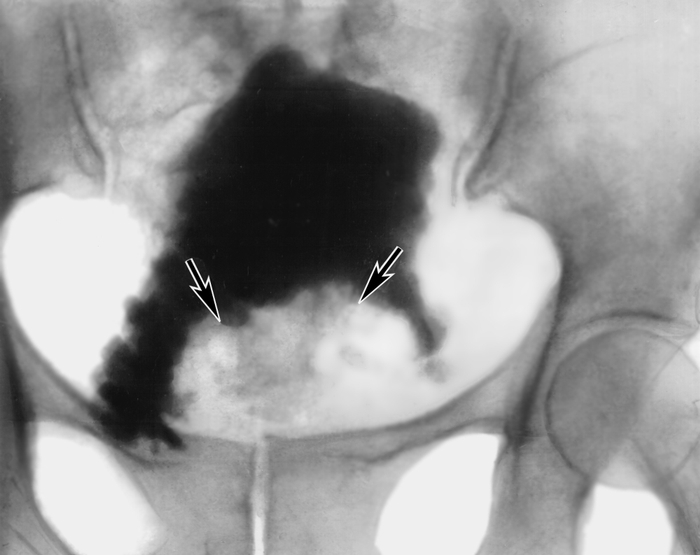

Медицинские изображения и примеры эксреторной цистографии